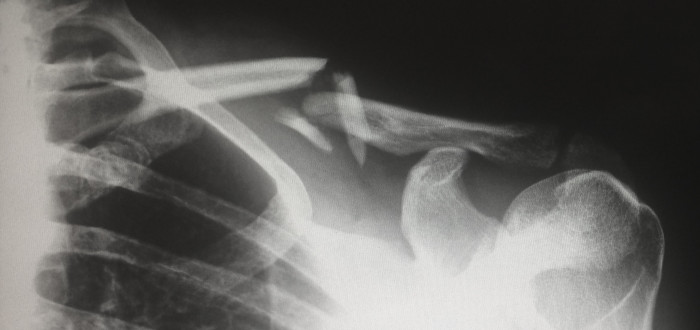

Ke zlomeninám, způsobených tímto onemocněním, dochází zejména v zápěstí, kyčlích nebo v páteřních obratlech.